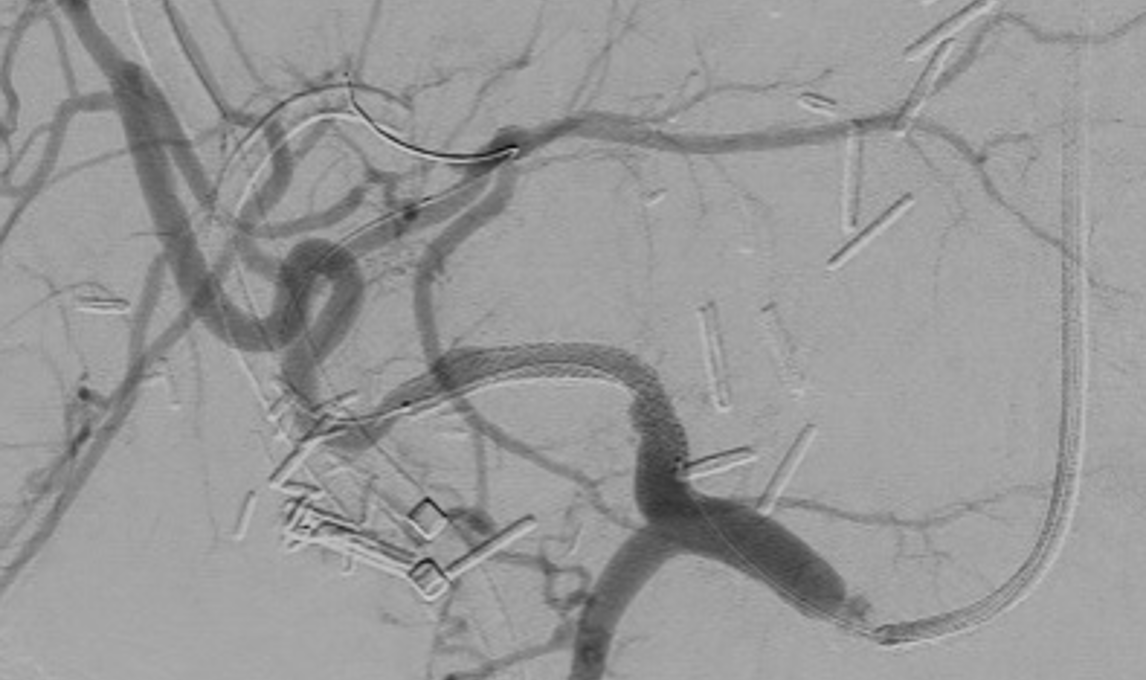

Stent placement is a suboptimal mechanical solution to chronic venous disease. We are doing translational research using a sheep model to study potential gene therapy strategies to minimize post-thrombotic venous changes and ameliorate the downstream quality-of-life complications.

- Reference: Li, N., Ferracane, J., Andeen, N., Lewis, S., Woltjer, R., Rugonyi, S., Jahangiri, Y., Uchida, B., Farsad, K., Kaufman, J.A. and Al-Hakim, R.A., 2022. Endovascular Venous Stenosis and Thrombosis Large Animal Model: Angiographic, Histological, and Biomechanical Characterizations. Journal of vascular and interventional radiology: JVIR, 33(3), pp.255-261. https://doi.org/10.1016/j.jvir.2021.10.036

Our research utilizes advanced flow imaging and computational fluid dynamics modeling to map complex blood flow patterns in healthy, diseased, and stented veins. We aim to uncover how chronic venous disease and interventions like stent placement alter hemodynamics, providing critical insights to optimize treatments for conditions like iliac vein compression (May-Thurner) syndrome and post-thrombotic sequelae.

- Reference: Li, N., Ferracane, J., Andeen, N., Lewis, S., Woltjer, R., Rugonyi, S., Jahangiri, Y., Uchida, B., Farsad, K., Kaufman, J.A. and Al-Hakim, R., 2022. Impact of Postthrombotic Vein Wall Biomechanics on Luminal Flow during Venous Angioplasty and Stent Placement: Computational Modeling Results. Journal of vascular and interventional radiology: JVIR, 33(3), pp.262-267. https://doi.org/10.1016/j.jvir.2021.12.006